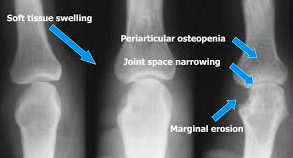

• Raised inflammatory markers (CRP and ESR)

• Plain raidiograph with LESS

Give NSAIDs, start DMARDs or biologics